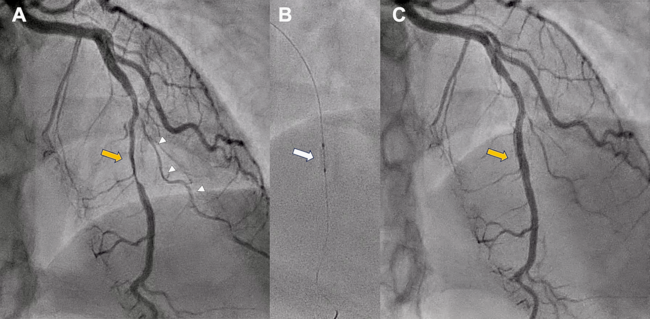

A 37-year-old woman with no prior medical history was admitted with a non-ST-segment elevation myocardial infarction. Despite initial medical therapy, she developed refractory chest pain, T-wave inversion in the precordial leads, and anterior wall akinesia on echocardiography. Emergent coronary angiography revealed a long, smooth, and diffuse narrowing of the mid-left anterior descending artery (LAD), characteristic of type 2 spontaneous coronary artery dissection (SCAD), along with features of type 3 SCAD in a small second diagonal branch (Figure 1A).

Given ongoing ischemia and hemodynamic stability, a percutaneous coronary intervention was performed with a deliberate stent-avoidance strategy. A cutting balloon was used to fenestrate the intramural hematoma and decompress the false lumen (Figure 1B), achieving full restoration of LAD flow and complete resolution of symptoms (Figure 1C). No stents were implanted. Coronary computed tomography angiography before discharge confirmed a patent LAD without intramural hematoma or atherosclerosis (Figure 2).